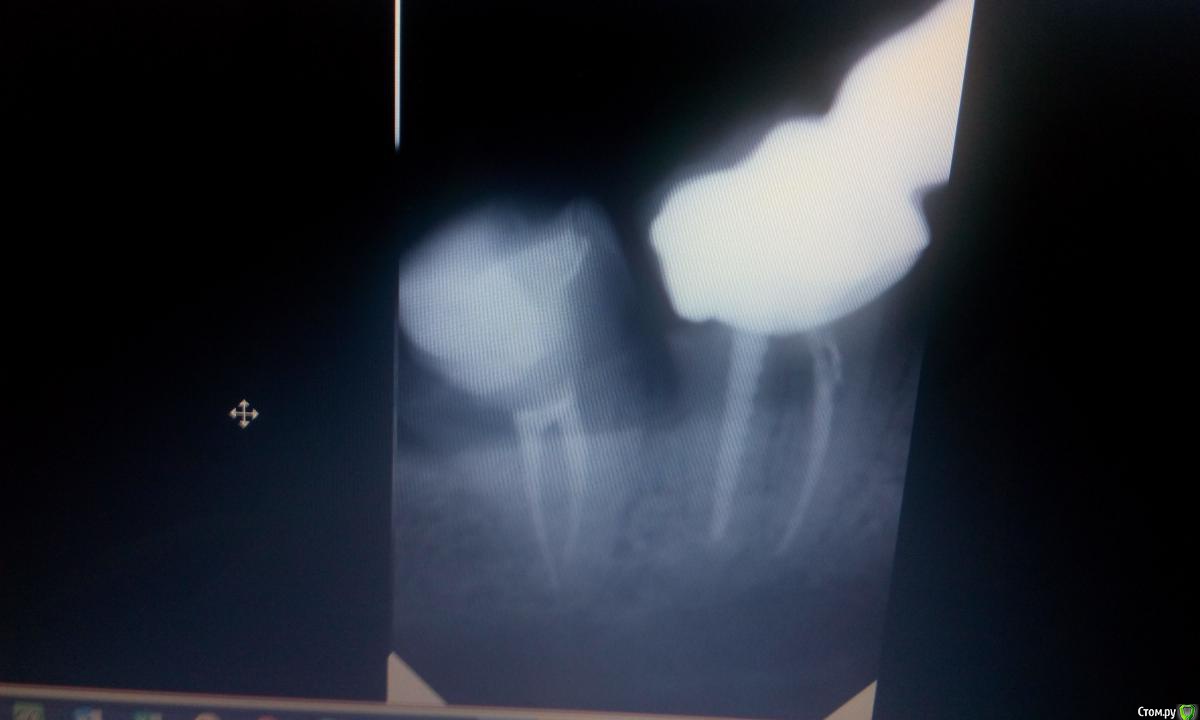

Витторио Орлионе Опубликовано 27 июля, 2016 Поделиться Опубликовано 27 июля, 2016 Обратилась пациентка с жалобами на боль в области зуба 4.8. При осмотре было обнаружено, что дистальная стенка зуба скололась под десну на глубину 4мм и вызвала воспаление десны, что пациентку и привело в клинику. Рядом протянулся мостовидный протез 4.7-4.5 и именно между зубами 4.8 и 4.7 полностью отсутствует контакт и постоянно застревает пища. А после того как сделали снимок было ещё и обнаружено нарушение прилегания коронки зуба 4.7 к его корню.Как мне кажется самым оптимальным было бы удаление зуба 4.8, но вопрос в том а вдруг он понадобиться как опорный для изготовления мостовидного протеза 4.8-4.5??Какова ваша тактика лечения в этом случае уважаемые коллеги: удалить 4.8 и оставить мостик как есть или же если это возможно изготовить новый мостик? Ссылка на комментарий

red_butler Опубликовано 27 июля, 2016 Поделиться Опубликовано 27 июля, 2016 снимок плохой, проведите зондирование десневой борозды у седьмого, похоже он свое доживает. Мудрый конечно в плевашку. Ссылка на комментарий

Витторио Орлионе Опубликовано 27 июля, 2016 Автор Поделиться Опубликовано 27 июля, 2016 и ещё в 7ом в дистальном канале такой мощный анкер стоит! Значит надо будет его доставать и перелечивать а потом массивную вкладку туда же и ставить? Ссылка на комментарий

DrNice Опубликовано 27 июля, 2016 Поделиться Опубликовано 27 июля, 2016 в том то и дело, может пускай тогда и доживает, а то получится так что я всю эту конструкцию сниму, а потом человек без зубов останется до самой имплантации?Да и ещё в 7ом в дистальном канале такой мощный анкер стоит! Значит надо будет его доставать и перелечивать а потом массивную вкладку туда же и ставить?Да, анкер действительно массивный, достать его без последствий будет очень тяжело. Лучше рассмотрите вариант с удалением и имплантацией. Ссылка на комментарий